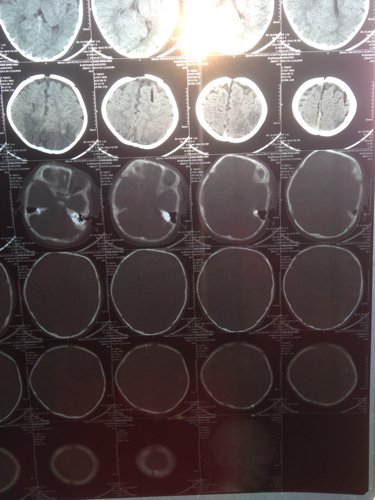

宝宝出生时被诊断为轻度缺血缺氧性脑病,住院治疗一个疗程,现在宝宝5个月复查做了CT,麻烦专业人士给

宝宝出生时被诊断为轻度缺血缺氧性脑病,住院治疗一个疗程,现在宝宝5个月复查做了CT,麻烦专业人士给看看,谢谢

问题分析: 新生儿窒息很容易引起缺血缺氧性脑病,如果当时没有抽搐,肌张力正常,精神状态好的话,应该是轻度的。 意见建议: 如果有条件可以给与第二疗程的神经节苷评裕脂,这样效果好,如果没有条件,多给孩了射暖子进行康复训练,孩高究子的可塑性很大。